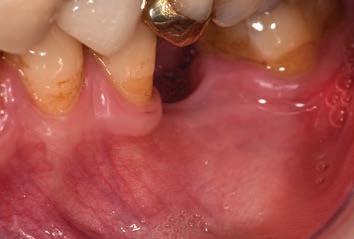

The third step of the treatment consisted of the crown lengthening, necessary to expose an adequate part of the root to obtain, after healing, the correct adhesion of the composite for the pre-prosthetic restoration and the successive prosthetic rehabilitation.

After the surgical flap elevation of the tissue and the bone remodeling, the flap was repositioned apically and sutured with a vertical mattress suture anchored in the periosteum (Figs. 5-6). The suture was removed after 7 days (Fig. 7).

glass fibre Figure 3: Root canal therapy completed under proper isolation. Figure 4: Radiography of completed root canal therapy and reconstruction made completely in glass hybrid cement. Figure 5: Clinical crown lengthening with a minimally invasive technique without mesial and distal discharges. Note the proximity of the reconstruction in glass hybrid material to the mesial bone ridge. Figure 6: Suture at the end of surgical therapy. It was left in place for 7 days Figure 7: Suture removal at 7 days. Post-surgical edema is still present.